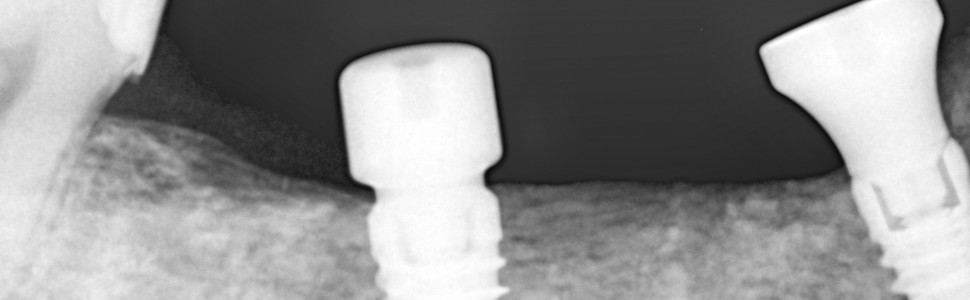

Szeroko praktykowana w implantologii chirurgia regeneracyjna ma na celu jak najefektywniejsze odtwarzanie zaników kości wyrostków zębodołowych potrzebnych dla zapewnienia optymalnych warunków implantacji. W chwili obecnej stosuje się ogromne spektrum metod służących poprawie kształtu i objętości wyrostków, jednakże żadna z nich nie zapewnia stuprocentowej przewidywalności i powtarzalności. Rozmaite zabiegi augmentacyjne mogą znacznie obciążać pacjenta i stanowić przyczynę niepowodzeń lub powikłań. Ponadto inwazyjność niektórych metod rekonstrukcyjnych może zniechęcać do ich przeprowadzenia zarówno operowanych jak i operatorów. W dobie minimalizowania ingerencji chirurgii w organizm człowieka, poszukuje się takich właśnie technik i materiałów, które mogłyby sprostać oczekiwaniom pacjentów i lekarzy w tym aspekcie, a jednocześnie zapewnić jak największą efektywność kliniczną. Dlatego autorzy chcieliby zaprezentować 3 przypadki zastosowania cementu regeneracyjnego z dwufazowym siarczanem wapnia i hydroksyapatytem w odtwarzaniu deficytów kostnych w szczęce i żuchwie.

Regenerative surgery, widely practiced in implantology, is aimed at the most effective reconstruction of alveolar bone loss needed to ensure optimal implantation conditions. Currently, a huge range of methods are used to improve the shape and volume of alveolar ridges, but none of them ensures 100% predictability and effectiveness. Various augmentation procedures can significantly burden the patient and cause failures or complications. Moreover, the invasiveness of some reconstructive methods may discourage both patients and operators from performing them. In the era of minimizing surgical intervention in the human body, we are looking for techniques and materials that could meet the expectations of patients and doctors in this aspect and, at the same time, ensure the greatest possible clinical effectiveness. Therefore, the authors would like to present a 3 cases of the use of regenerative cement with biphasic calcium sulfate and hydroxyapatite in the reconstruction of a bone deficit in the lateral mandible and frontal maxilla.